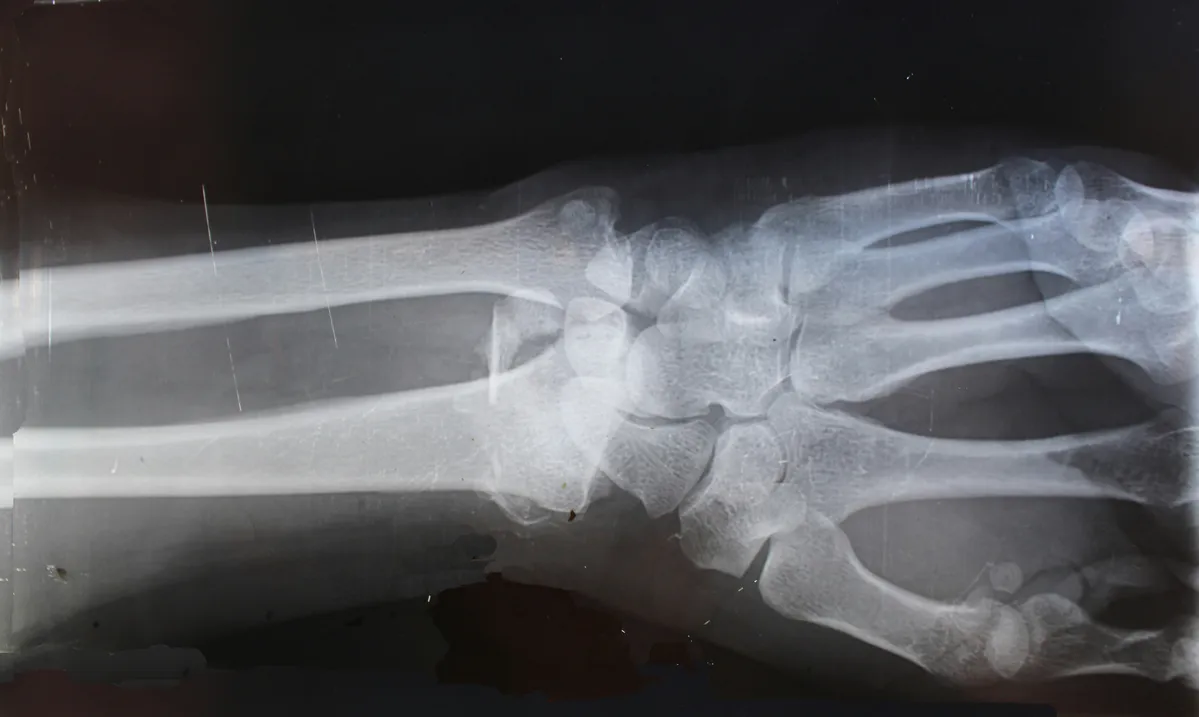

• Medical Records: Obtain all records of your medical treatment, including doctors' reports, X-rays, and any other relevant documents. This is one of the most important pieces of evidence.